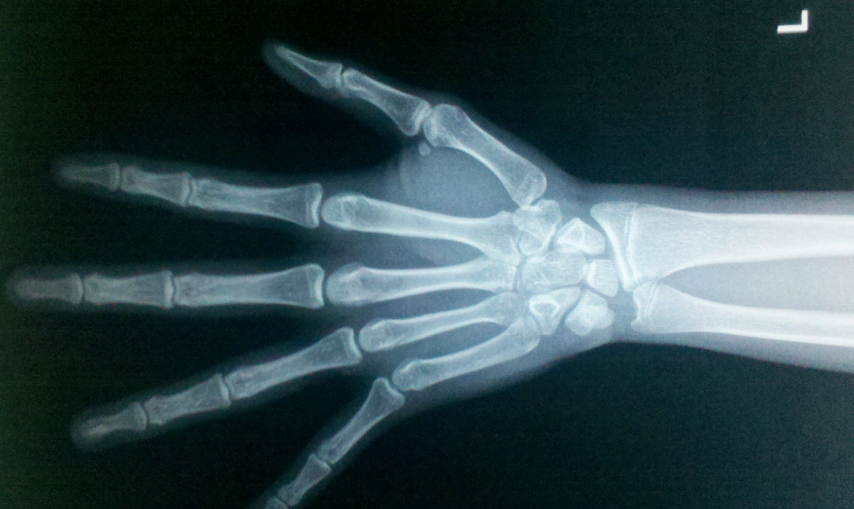

骨龄是可以反映儿童生长发育情况的重要指标,如果孩子身材矮小,医生一般会建议家长带他们去拍骨龄片。骨龄片会显示出骨化中心的发育情况,医生也可以据此来判断孩子的骨龄是否正常。那么什么时候拍骨龄片最好?

如果孩子的身高并没有明显的发育异常,想要拍摄骨龄片一般建议是在5~6岁以后。如果年龄过小,骨龄值可能会出现比较大的差异,容易影响检测结果的准确性。随着年龄增长,骨骼的发育越来越完善,进行骨龄检测时可以得出更为准确的结果。如果发现孩子的身高不足,5岁之后要尽早检查骨龄,以便及时发现问题,拖延的时间越长,问题可能会越严重。

如果孩子的身高发育情况存在着明显异常,比如身高明显落后于同龄同性别人身高超过10厘米,出现与自身年龄并不相符的身材矮小,需要及时进行骨龄检测。这种情况很有可能是生长发育迟缓造成的,不排除是生长激素缺乏症或者甲状腺功能减退症,通过骨龄检测可以辅助诊断。除此之外,如果孩子的身高在一段时间内突飞猛进,明显高于同龄人,也要及时进行骨龄检测,判断是否有骨龄偏大的问题。

由于现在饮食条件明显改善,孩子平时的运动量又比较少,肥胖现象越来越明显。过于肥胖会导致体内堆积大量的脂肪,这些脂肪会产生芳香化酶,导致雌激素过度转化。一旦出现这种情况,便有可能会发生性早熟,性早熟会使骨骼过度成熟,容易加速骨骺线的闭合。及时拍摄骨龄片可以判断骨龄是否偏大以及偏大的程度,并根据病情采取相应的干预措施,防止骨骺线过早闭合。

在正常情况下,女孩青春期的到来时间是在10~12岁之间,男孩稍晚一些,通常是在12~14岁之间。青春期到来后第二性征开始发育,身高也会突飞猛进,如果在这之前便出现发育现象,特别是女孩8岁之前发育,男孩9岁之前发育,需要引起足够的重视,尽早拍骨龄片。根据骨龄的检查结果判断骨骼的成熟度,并预测成年后身高是否会受影响。如果成年后身高受影响较大,则需要及时用药治疗,一般是使用促性腺激素释放激素类似物联合生长激素。